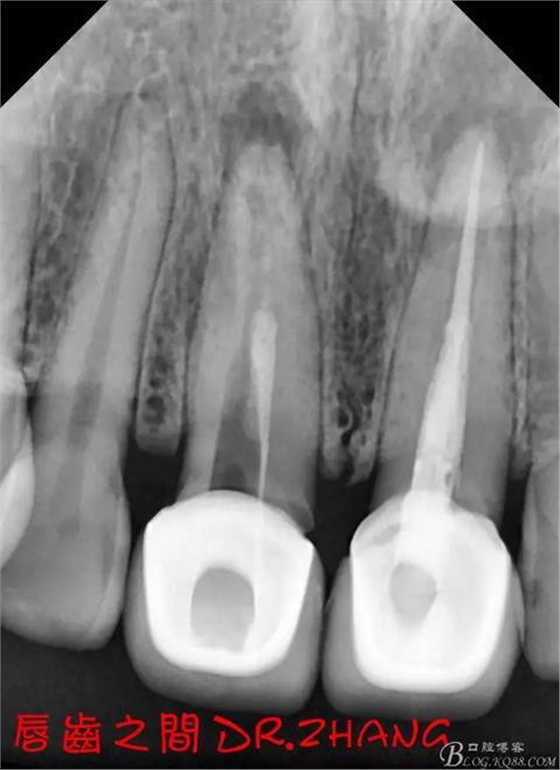

思博安熱牙膠系統(tǒng)根充 燙斷至根尖三分之一處后纖維樁恢復(fù)牙體組織

牙體預(yù)備后 硅橡膠取模 臨時(shí)牙恢復(fù)形態(tài)